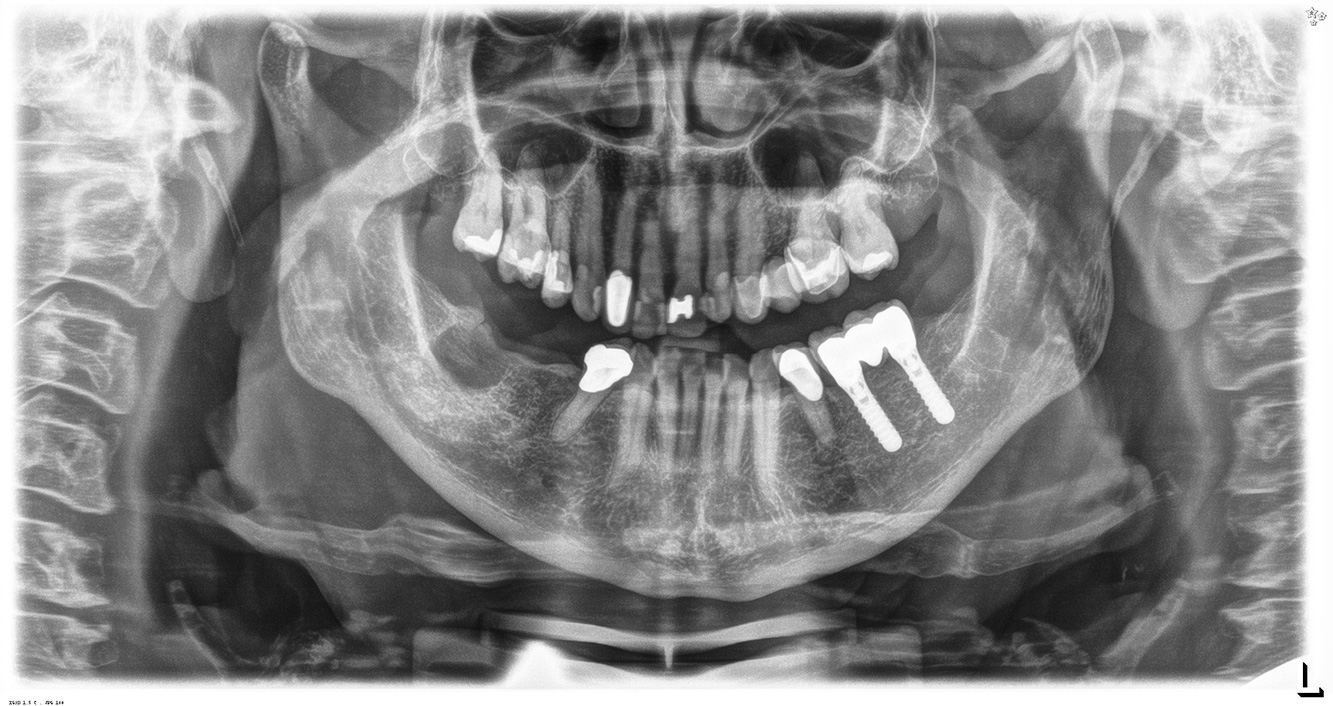

The (orally) healthy patient with implants

In the medical history, the 55-year-old patient states that he has no systemic disease and is not taking any medication. The patient’s lifestyle is similarly unremarkable. The patient has a few tooth restorations and two implants (2nd and 4th quadrants). On the basis of current findings, gingivitis is identified in an otherwise stable periodontal condition on the reduced periodontium (stage III, grade A). more